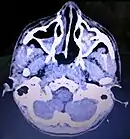

CT Brain showing air-fluid level in bilateral maxillary air sinuses post brain trauma. Maxillary sinusitis will also shows similar air-fluid collection and should be rule out from history taking.

Maxillary sinusitis is inflammation of the maxillary sinuses. The symptoms of sinusitis are headache, usually near the involved sinus, and foul-smelling nasal or pharyngeal discharge, possibly with some systemic signs of infection such as fever and weakness. The skin over the involved sinus can be tender, hot, and even reddened due to the inflammatory process in the area. On radiographs, there is opacification (or cloudiness) of the usually translucent sinus due to retained mucus.[8]